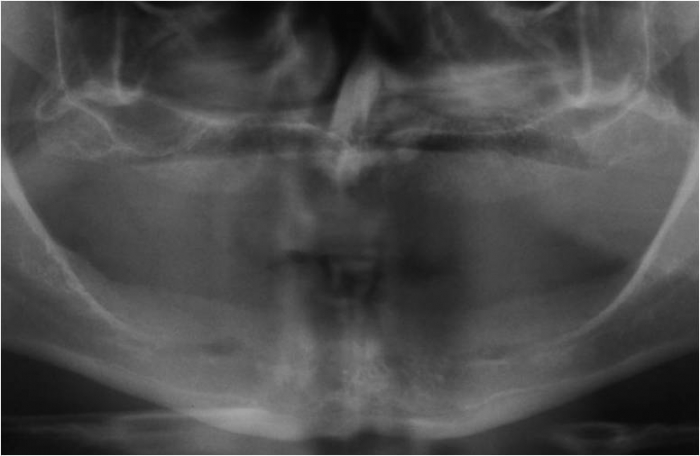

Rx do enxerto ósseo de maxila, com osso de crista ilíaca